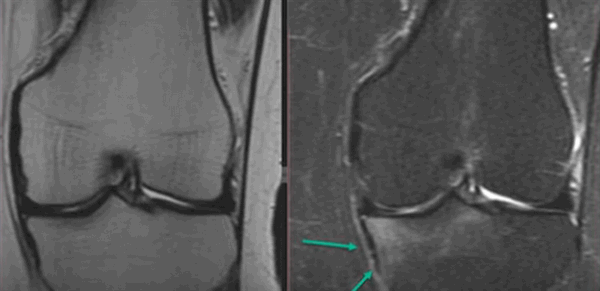

Явление ядерно-магнитного резонанса позволяет досконально изучить мягкие ткани. Кости на снимках видны недостаточно хорошо (по сравнению с КТ или рентгеном). Что дает МРТ коленного сустава? Исследование помогает выяснить сведения об окружающих сочленение структурах, по состоянию которых определяют скрытые (субхондральные) переломы: их нельзя или крайне трудно увидеть при рентгенографии. Полипроекционность, высокая разрешающая способность и возможность использования разных режимов сканирования — преимущества МРТ перед другими методами.

Субхондральный перелом латерального мыщелка на МРТ (указан стрелками)

Врач оценивает положение каждого элемента сочленения, размеры, четкость контуров и выявляет любые отклонения от нормы. По МРТ коленного сустава обнаруживают:

- скрытые костно-травматические изменения;

- патологии хрящевой ткани (повреждения, дегенерацию);

- травмы связочного аппарата (разрывы, растяжения);